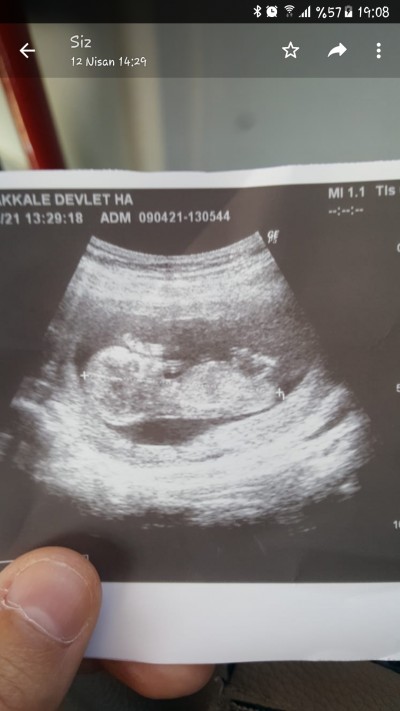

Kizlar ilk gittiğimde 11 haftalık ti belli değildi.cinsiyeti şuan 12.5 cuma günü ikili testim var acaba cinsiyeti belli olur mu .ne aceleniz var demeyin lütfen merak işte.lutfen kalp kırıcı konuşmayalım.zaten riskli bı gebeliğim var ennbasindan beri çok analmiorum bundan görünen ayakları olsa kolları nerde burnu mu ağzımı görünen Dr pek bilgi vermior baş popo ölçüm eline bunu verip yoluyorlar tahmin bile etmiorlar

Gebelik haftası 12+5

Tabikidesaglik onmli ama bakiorum sürekli yüzü belli gibi 2 ayak mi bacakmi gorunuor o sadce merak dediğiniz gibi önce sağlık rabbim kucagimiza almayı nasip etsin .

Erkeğe benzettim açıkçası benimki de bu şekildeydi  ve erkek